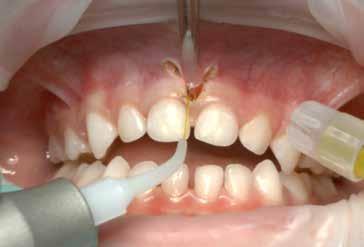

S.V. Paziente di tre anni di sesso maschile, in III Classe scheletrica lieve, con open-bite, deglutizione atipica, contrazione dell’arcata superiore, tendenza alla III Classe. Alla prima visita il paziente presentava un evidente frenulo vestibolare corto, a tetto labiale che, trazionando il labbro superiore, tendeva a ischemizzarsi insieme alla papilla retroincisiva.

In situazioni simili si potrebbe anche attendere ma, poiché si rendeva necessaria una terapia ortodontica, si è proceduto ad eseguire una frenulectomia e il giorno stesso è stato consegnato al paziente l’apparecchio elastodontico per la correzione della malocclusione. Lo scudo vestibolare dell’apparecchio ha contribuito alla guarigione del frenulo stesso determinando una trazione continua sul labbro superiore.

La sequenza terapeutica ha previsto i seguenti step:

• frenulectomia laser;

• terapia elastodontica al fine di ripristinare la corretta crescita scheletrica e dentale.

Fig. 4

Fig. 5 > Immagine intraorale frontale.

Fig. 6 > Immagine intraorale laterale destra.

Fig. 7 > Immagine intraorale laterale sinistra.

Fig. 8 > Dettaglio del frenulo labiale superiore corto.

Figg. 9-11 > Intervento di frenulectomia con laser a diodo.

Figg. 12, 13 > Controllo dopo ventiquattro ore.